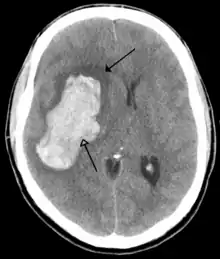

![]() | |

| CT scan of the brain showing a massive, prior right-sided ischemic stroke from blockage of an artery. Changes on a CT may not be visible early on.[1] | |